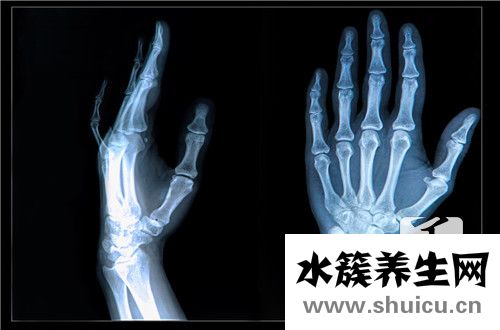

橈骨遠端骨折非常常見,約占平時骨折的1/10。多見于老年婦女,青壯年發生均為外傷暴力較大者。骨折發生在橈骨遠端2~3cm范圍內。常伴橈腕關節及下尺橈關節的損壞。

腕部腫脹、壓痛明顯,手和腕部活動受限。伸直型骨折有典型的餐叉狀和槍刺樣畸形,尺橈骨莖突在同一平面,直尺試驗陽性。屈曲型骨折畸形與伸直型相反。注意正中神經有無損傷。